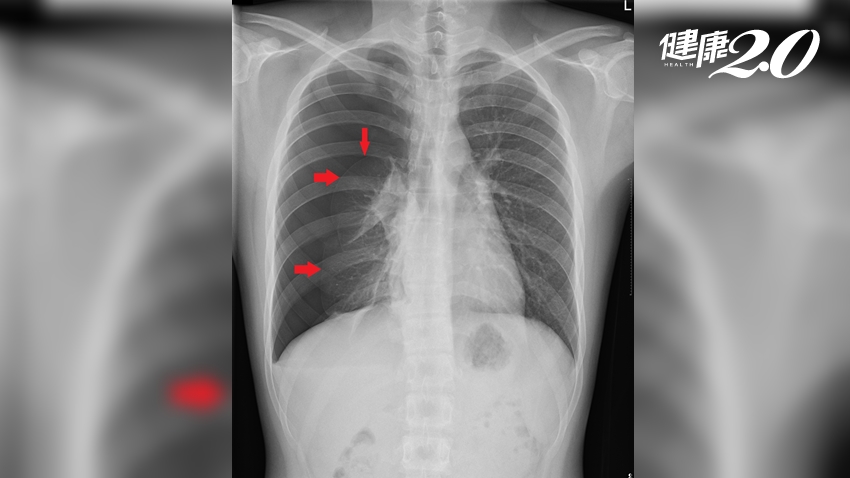

別以為「胸痛」就是心臟有問題。一位身材高瘦、愛打籃球的高中生,日前在打球時突然感到右胸疼痛,症狀緩解後沒再多理會;後來某次打球時右胸突發劇痛,開始喘且呼吸困難,被小型醫院診斷為「氣胸」,轉往大醫院緊急處置後,醫師表示,還好患者即時就醫,否則可能引發休克。

夏肇聰 進一步解釋,氣胸是因為肺臟的肺泡破裂或是囊腫破裂,使空氣從肺泡進入肺臟與胸壁之間的腔室,造成氣體在肋膜腔內蓄積,壓迫到肺臟,造成肺臟無法擴張,進而引起胸悶、胸痛、氣喘等症狀。如果輕忽,可能會進一步惡化成「張力性氣胸」,導致心臟受到壓迫,血液無法回流到心臟,引發休克,嚴重者甚至會死亡。